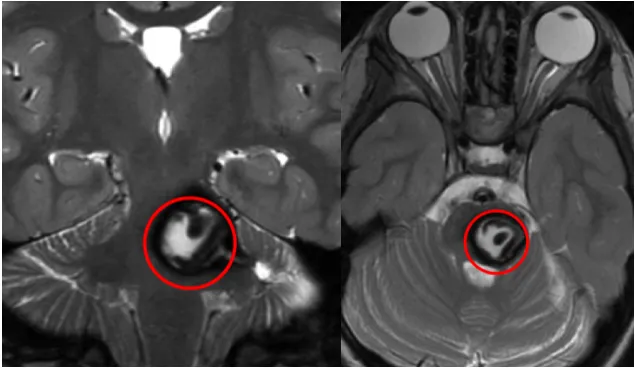

图示:莉亚颅脑MR显示中脑占位,信号混杂,符合海绵状血管瘤特征。